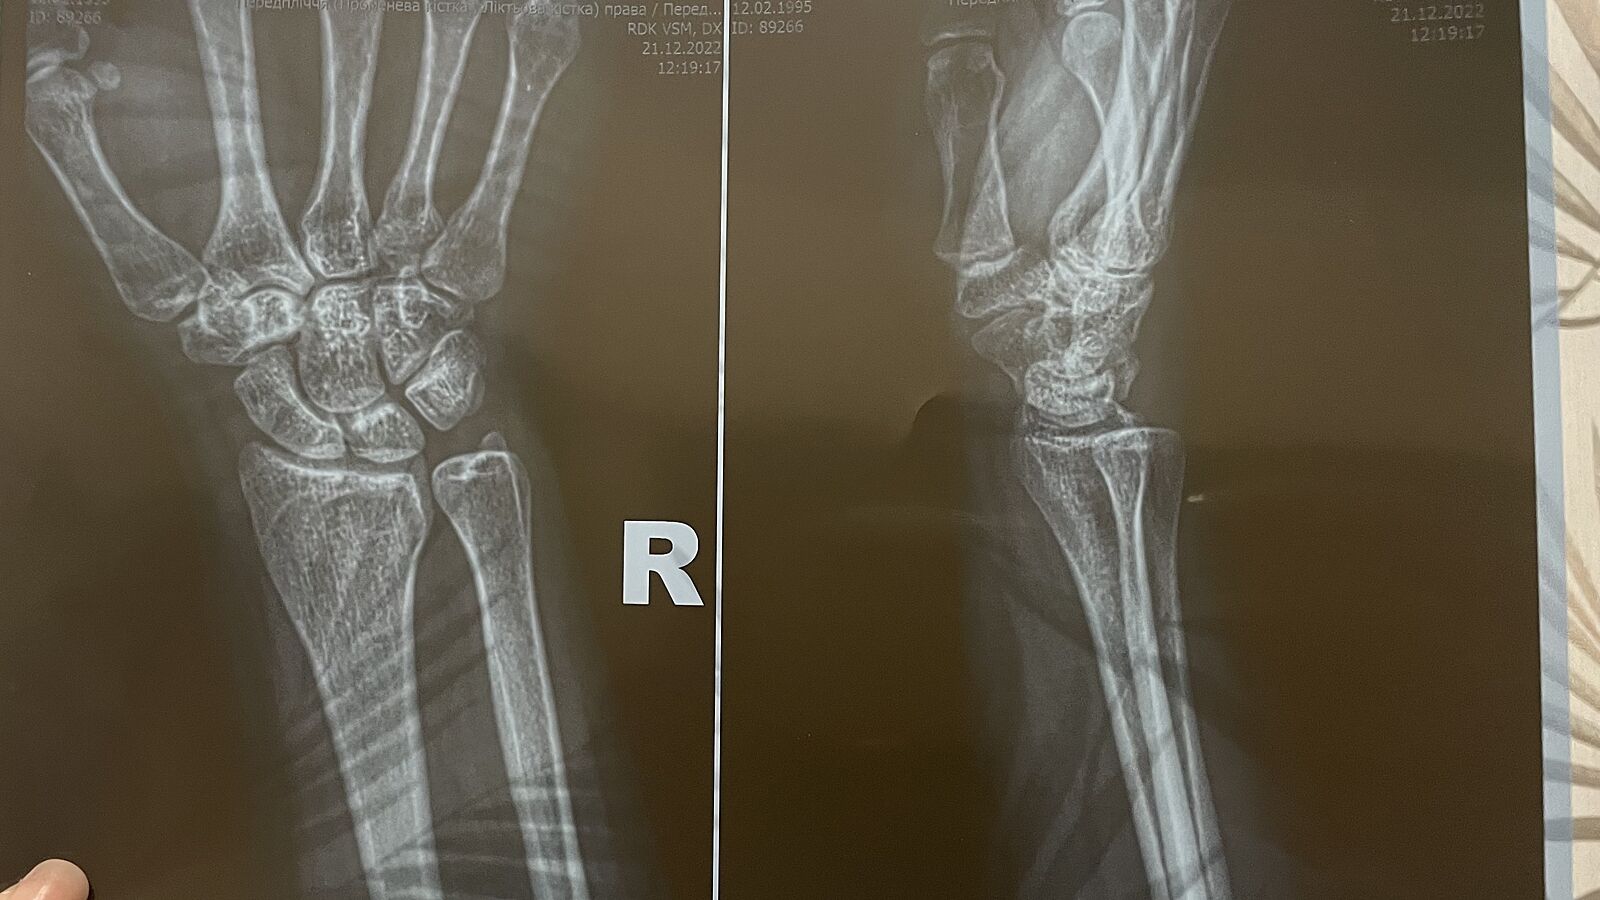

Хто розбирається у знімкках чи є перелом?

По діагнозу - перелом шилоподібного відростка правої променевої кістки

Просто є дві протилежні думки

А можете обвести де саме? Бо є дві протилежні думки, а я не бачу де саме

Один лікар сказав, що перелом інший нічого не побачив

Я не виду перелома

Не вижу

Все прям такие врачи, всем видно))) П.с. я не врач, но тут ничего не могу сказать и особенного ничего не вижу. У меня как был перелом, то на снимке было видно, что кость пошла в другую сторону

Я правда лікар акушер-гінеколог, але я не бачу перелому шилоподібного відростку

Однозначно, перелома нет.

Возможно, что есть